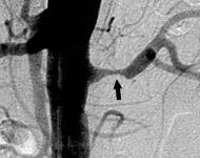

Эталонным методом диагностики стеноза почечных артерий служит селективная почечная артериография. По полученным ангиограммах выявляется локализация и протяженность стеноза, определяются его причины и гемодинамическая значимость.